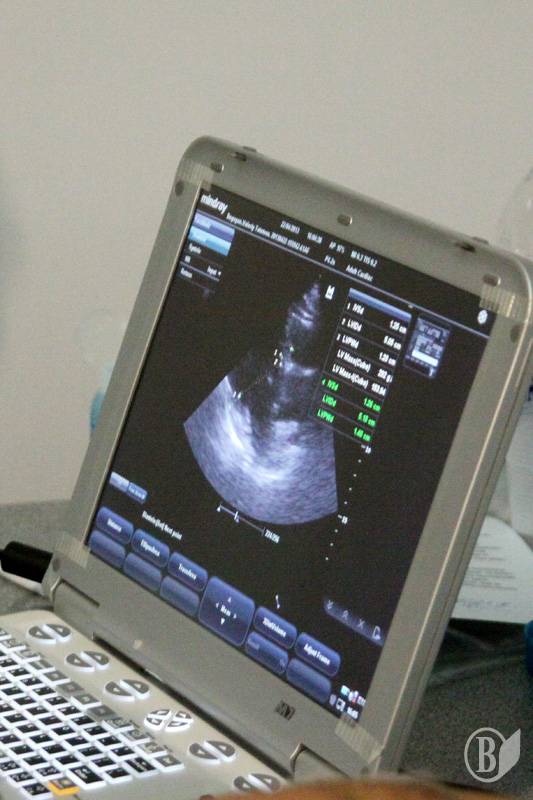

УЗД серця (ультразвукове дослідження) - безопераційне дослідження роботи і будови серця за допомогою ультразвукових хвиль. Це самий нешкідливий і безпечний спосіб виявлення серцево-судинних захворювань. Його можна робити як дорослим, так і дітям. Ультразвукова діагностика серця під час проекту «Відкрий своє серце» буде проводиться на ультразвуковому сканері Mindray M7.